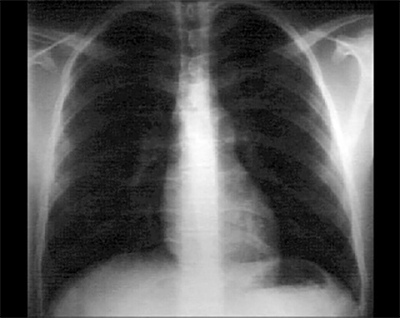

These chest X rays show a dilated pulmonary trunk. In this PA view, it is demonstrated by the convex density below the aortic knob. Note the normal pulmonary vascularity and heart size.